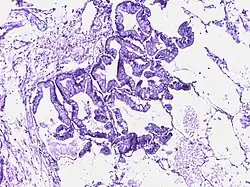

Adenocarcinoma colon | Micrograph of carcinoma colon showing malignant glands.Nuclei are small and vesicular, located at the bottom of the cell. The cells show increased nucleocytoplasmic ratio. | Category: Histopathology of colorectal adenocarcinoma | Colorectal carcinoma |

![]() |